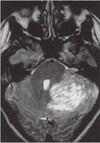

This MRI demonstrates evidence of what process? A. Metastases B. Alcoholic cerebellar degeneration C. Turcot’s syndrome D. Lhermitte-Duclos disease

A. Metastases B. Alcoholic cerebellar degeneration C. Turcot’s syndrome **D. Lhermitte-Duclos disease** ## Footnote This MRI demonstrates findings consistent with Lhermitte-Duclos disease, with evidence of hypertrophic cerebellar folia. Further Reading: Psaaros. The Definitive Neurosurgical Board Review, page 129.

What gene mutation is often linked with patients exhibiting the findings as shown under Question 29? A. P53 B. SHH C. PTEN D. H-ras

A. P53 B. SHH **C. PTEN** D. H-ras ## Footnote This MRI demonstrates findings consistent with Lhermitte-Duclos disease, with evidence of hypertrophic cerebellar folia. This finding can be seen in patients with Cowden’s syndrome, often caused by a mutation in PTEN. Further Reading: Psaaros. The Definitive Neurosurgical Board Review, page 129.